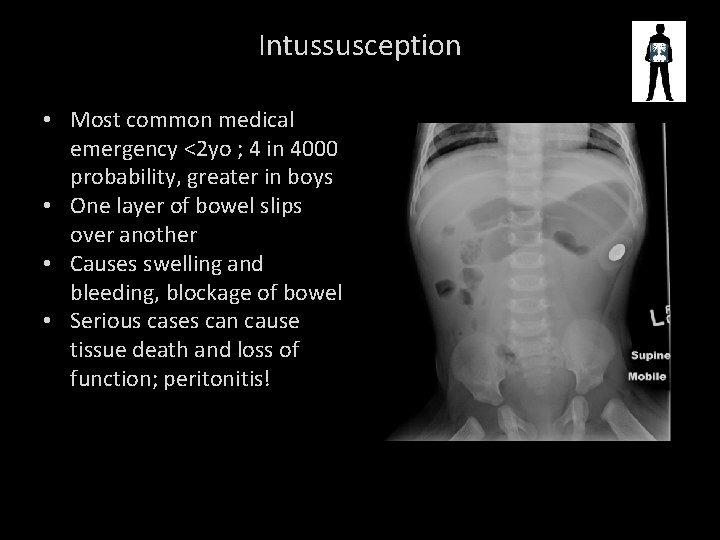

Intussusception

Intussusception • Most common medical emergency <2 yo ; 4 in 4000 probability, greater in boys • One layer of bowel slips over another • Causes swelling and bleeding, blockage of bowel • Serious cases can cause tissue death and loss of function; peritonitis!